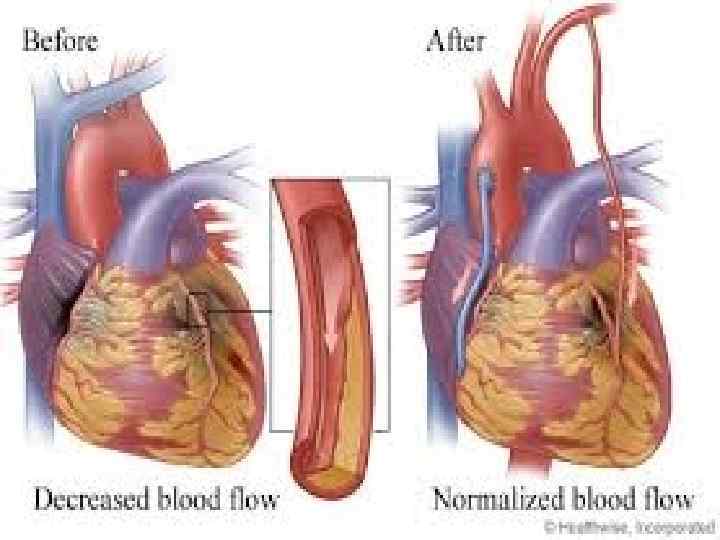

ХИРУРГИЧЕСКИЕ МЕТОДЫ ЛЕЧЕНИЯ. • Хирургическая реваскуляризация миокарда (ЧТКА, АКШ) улучшает выживаемость б-х ИБС с тяжелым течением иили прогнозом заболевания. Различают клинические и ангиографические показания их применения. Клинические показания – отсутствие эффективности медикаментозной терапии стенокардии, сохранение симптомов ИБС, резко ограничивающих физическую активность пациентов. Ангиографические показания: 1. Трехсосудистое поражение КА; 2. 2 -3 -сосудистое поражение КА в сочетании с дисфункцией ЛЖ; 3. Поражение ствола ЛКА; 4. ФВ<30% независимо от количества пораженных КА. Показания к применению ХМЛ у пациентов пожилого и старческого возраста следует определять тщательнее, чем у лиц среднего возраста из-за большего риска осложнений.